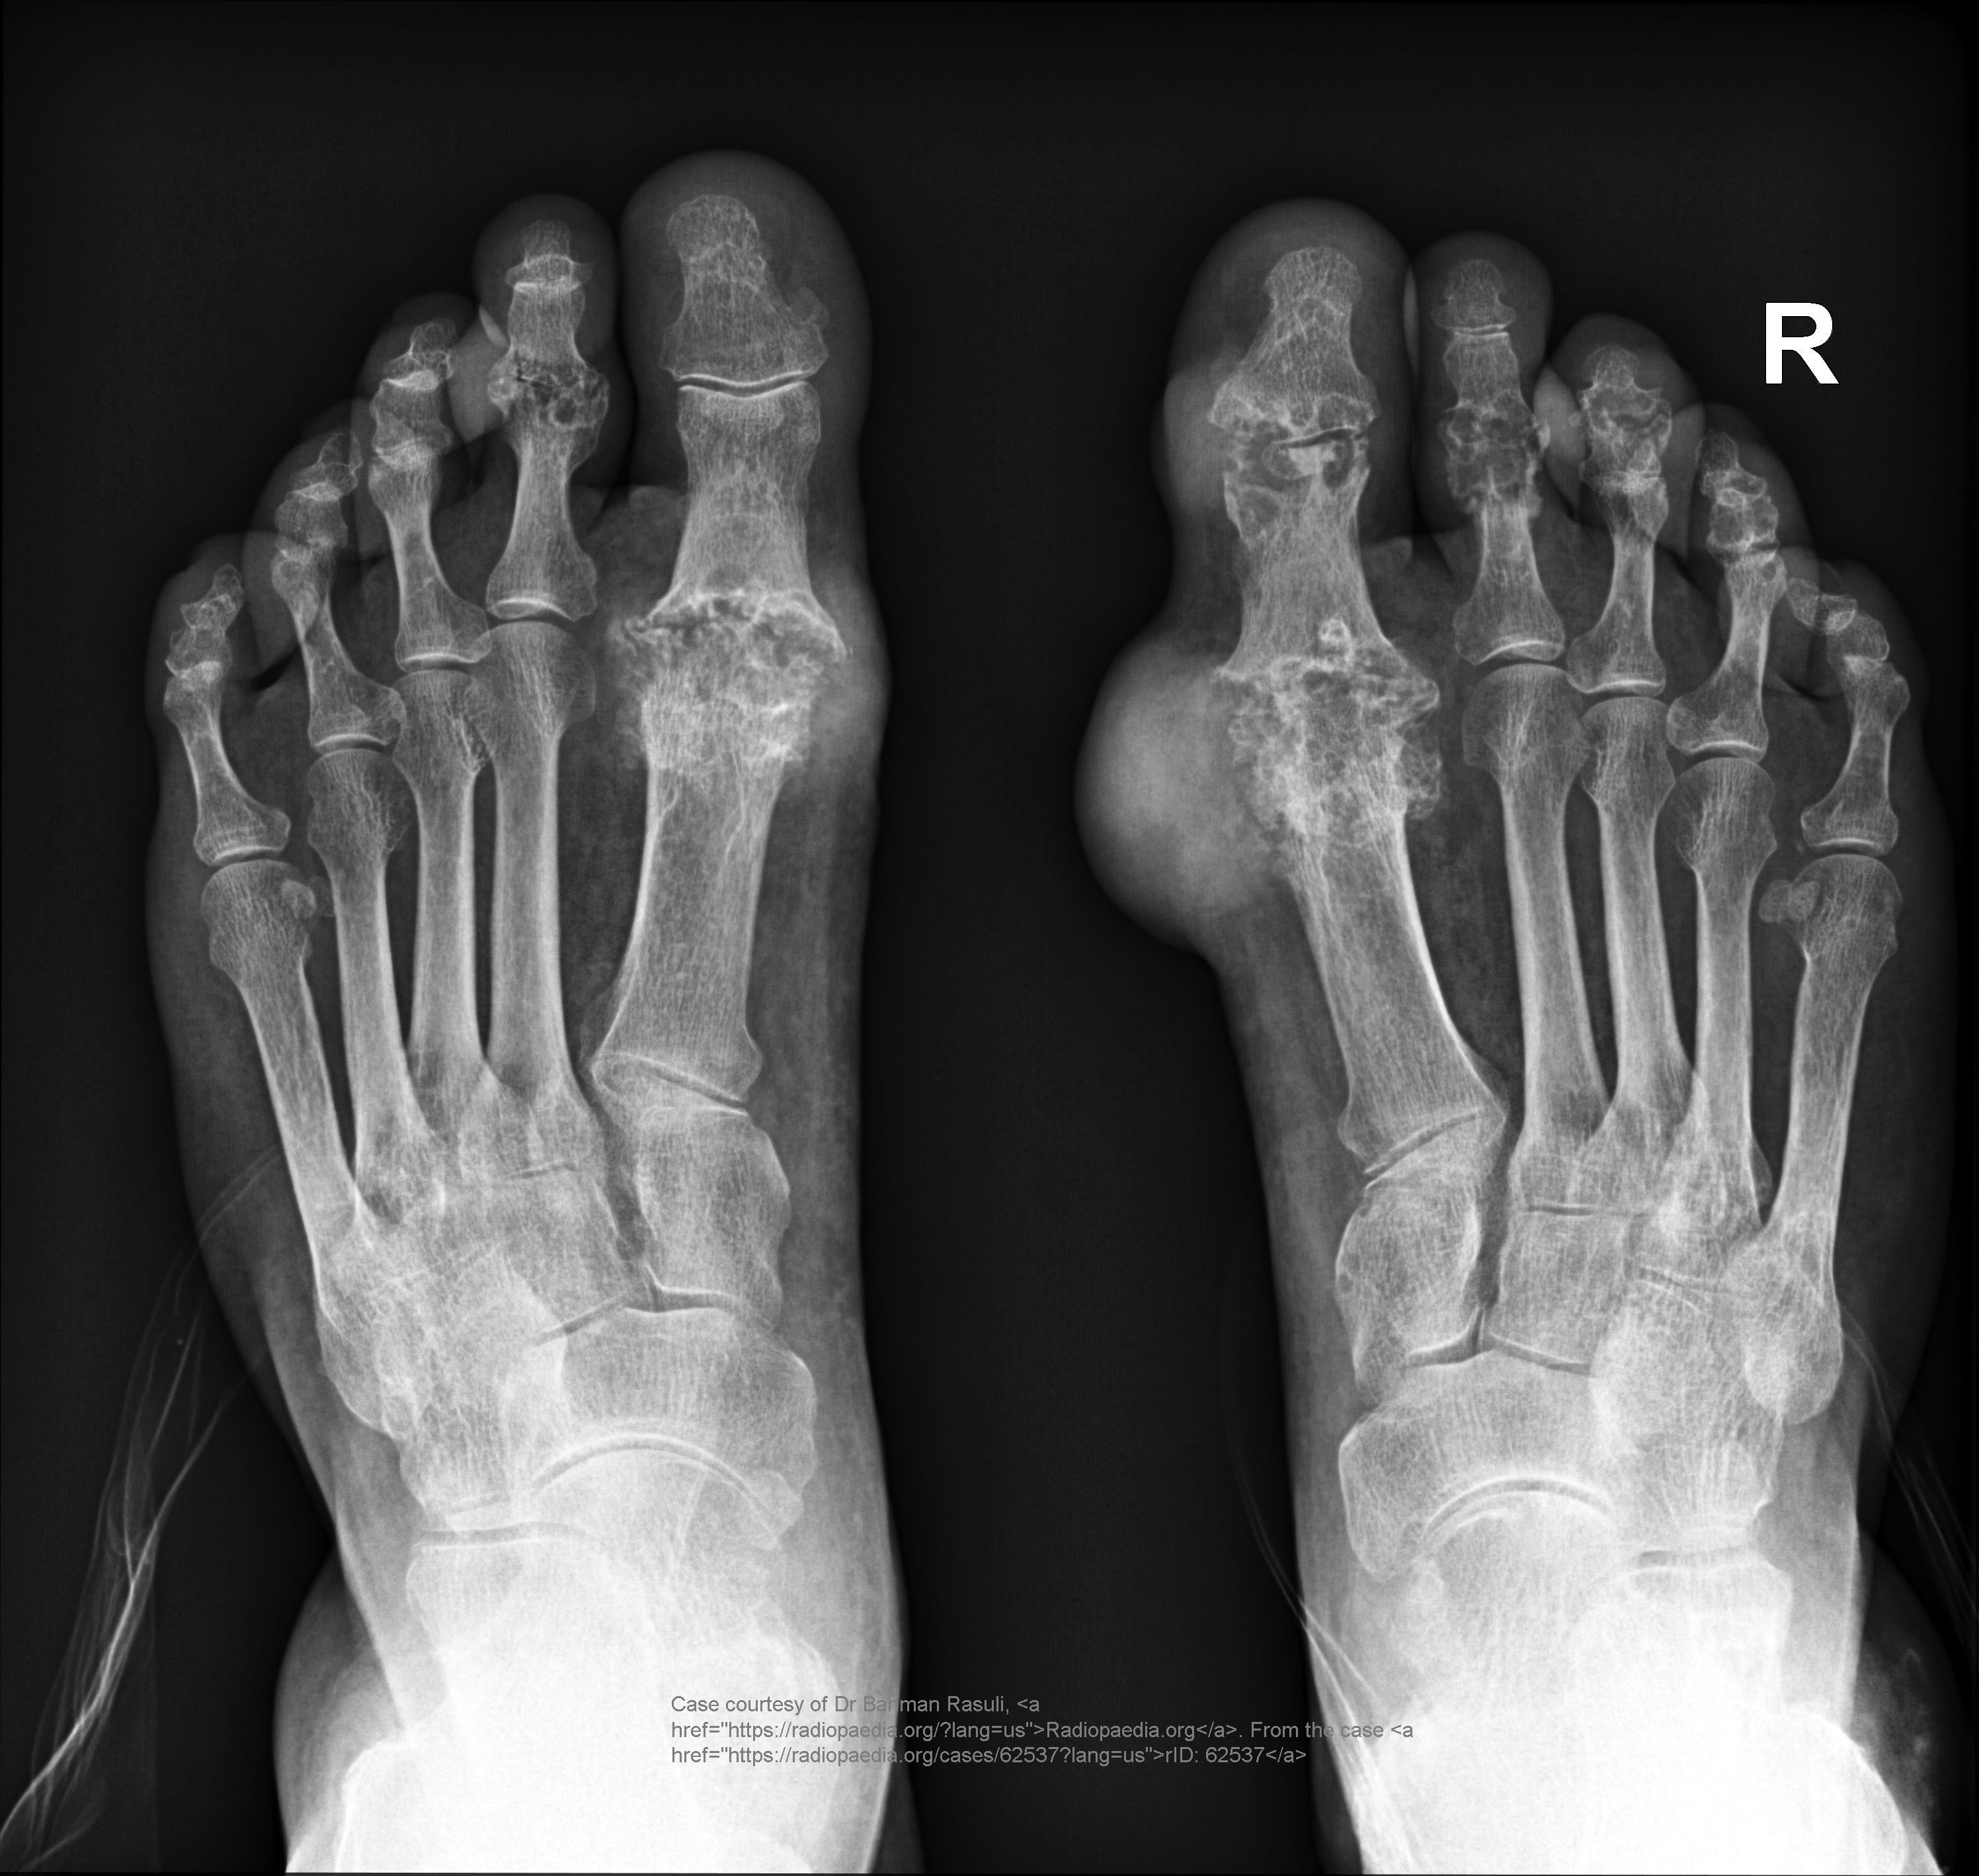

Common site for gout?

First MTP joint of the big toe.

Radiographic signs of gout?

Late changes: “mouse-bitten” erosions, overhanging edges, possible calcified tophi; no osteopenia.